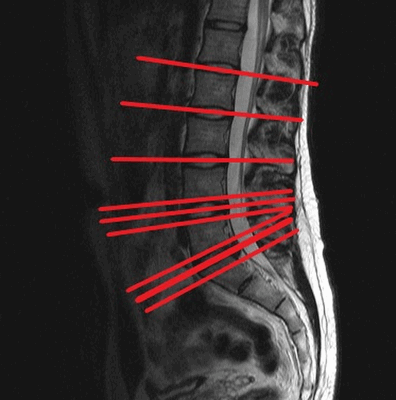

Постановка срезов при МР-сканировании для диагностики состояния межпозвонковых дисков

Несмотря на достаточную информативность рентгена для постановки диагноза при искривлении спины, врачи активно назначают и другие методы визуализации. Данное обстоятельство обусловлено необходимостью комплексной оценки состояния пациента для выявления причин и последствий деформации, чтобы правильно назначить лечение. Сколиоз признан тяжелым прогрессирующим заболеванием, которое приводит не только к изменению внешности больного, но и ко множественным функциональным нарушениям в организме. Главное, что дает МРТ позвоночника при сколиозе — это сведения о состоянии мягкотканных элементов позвоночного столба:

Причиной для назначения магнитно-резонансной томографии выступает наличие у пациента неврологической симптоматики. Сканирование позволяет обнаружить протрузии дисков, грыжевые выпячивания, признаки воспаления, компрессии нервов, миелоишемию и иные варианты местных нарушений кровообращения, инфекционные заболевания и т.п.